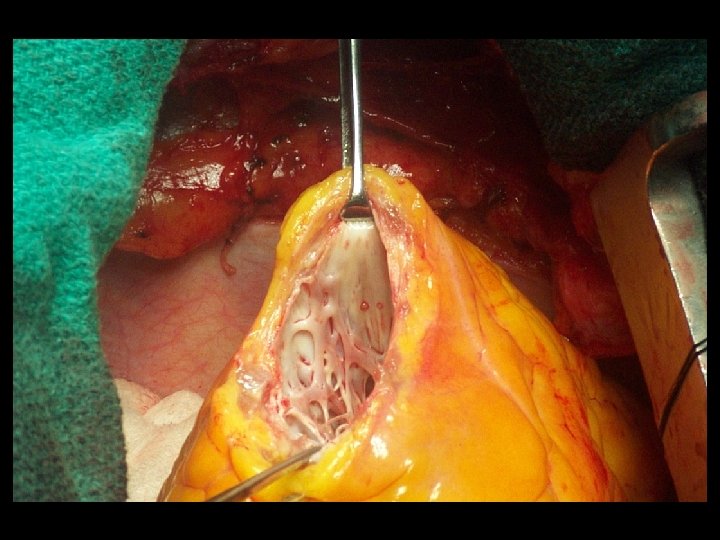

Técnica quirúrgica: cierre lineal o o Incisión en la porción mas delgada del aneurisma, paralela al surco interventricular. Excisión del área cicatricial. Suturas de tracción en cada extremo de la línea de sutura. Cierre del defecto con puntos en U separados de polipropileno No. 1 sobre líneas de felpa y refuerzo de sutura continua No. 0.

Técnica quirúrgica: plastia con parche o o Incisión en la porción mas delgada del aneurisma, paralela al surco interventricular. Jareta con sutura de polipropileno 2 -0 en la línea que demarca la cicatriz con el miocardio. Medida del defecto. Parche de dacron o pericardio (autólogo o bovino).

Técnica quirúrgica: plastia con parche o o Sutura continua del parche con polipropileno 3 -0. El remanente de la pared aneurismática es suturada linealmente sobre el parche con puntos continuos de polipropileno 2 -0.